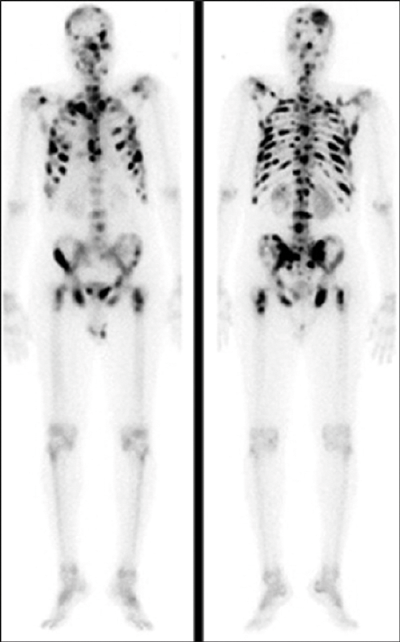

A 74-year-old gentleman is referred with a PSA of 238ng/ml. DRE reveals a hard nodular prostate.

- What type of radiological imaging is shown?

This is a bone scintigraphy or radionuclide whole body isotope bone scan.

Radiation exposure: 4-6 mSV.

The bone scan demonstrates ‘superscan’ due to extensive osteoblastic metastasis. When there is diffuse metastasis, all of the radiotracer is concentrated in the skeleton with little or no activity in the soft tissues or urinary tract.